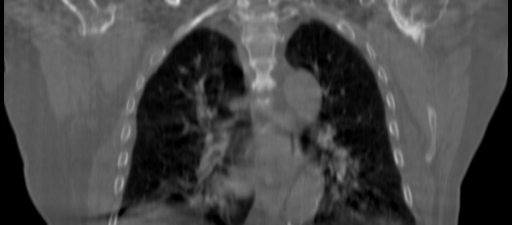

Planning CT Images

ClearRT® Images